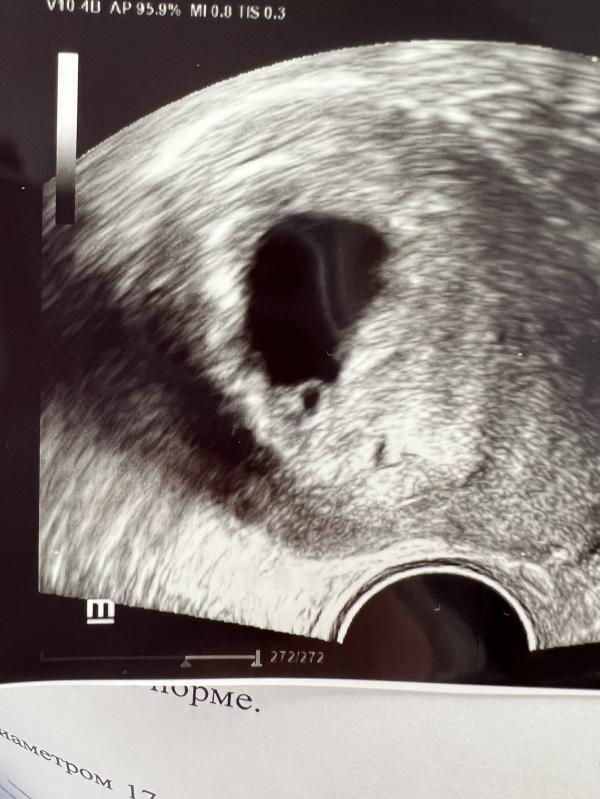

Сходила на узи, сердечко показали,стучит.